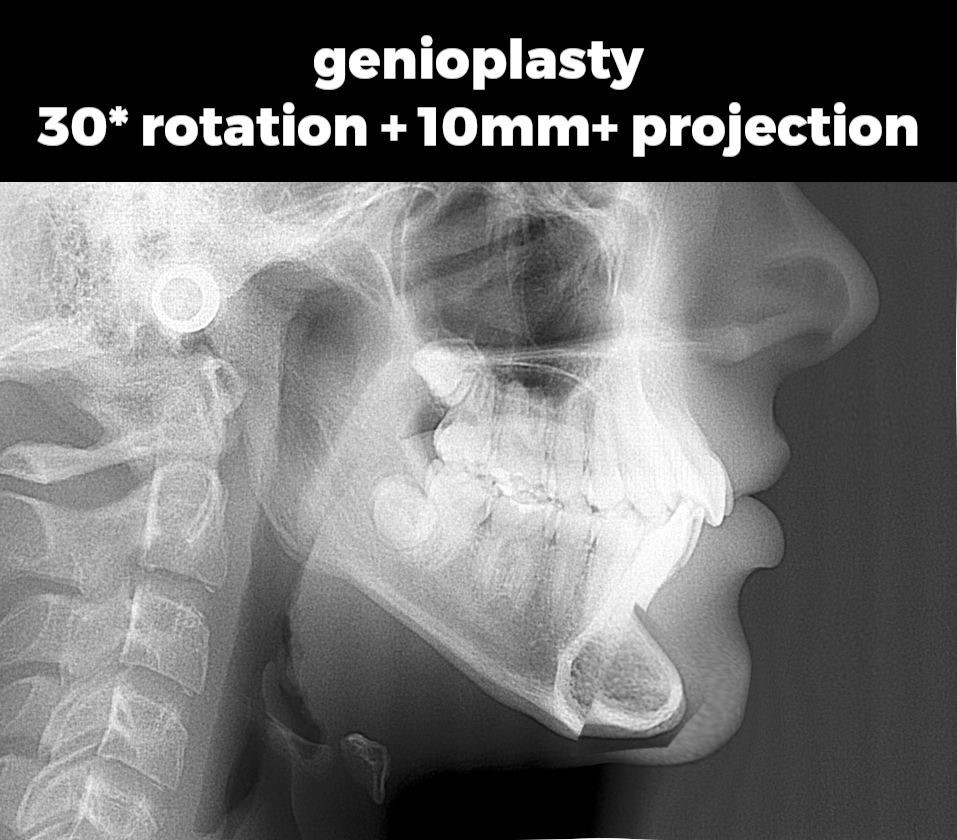

Example of such genioplasty in the case of a downgrown jaw

Dr John McHugh

Genioplasty: $3,000–$5,000 USD

Example of such genioplasty in the case of a downgrown jaw

Dr John McHugh

Genioplasty: $3,000–$5,000 USD